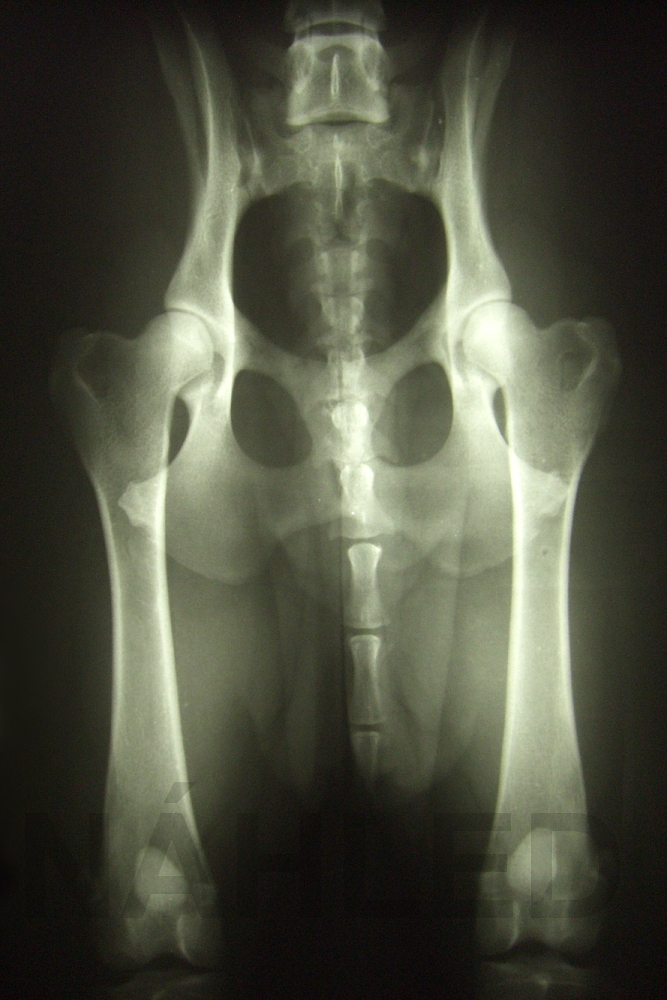

Vyšetření DKK

1. Vyšetření RTG DKK je jednou z podmínek pro zařazení do chovu.

2. Vyšetření se provádí po dovršení 12 měsíců či později.

3. Zhotovit rtg snímek kyčelních kloubů psa pro posouzení dysplazie kyčelních kloubů k získání podkladů pro potřeby chovu je oprávněn pouze veterinární lékař; člen Komory veterinárních lékařů České republiky a držitel osvědčení o splnění podmínek k výkonu veterinární léčebné a preventivní činnosti, který má k dispozici rtg pracoviště, na němž je možné zhotovit expozičně, projekčně a z hlediska identifikace správný snímek.

4. Posoudit rtg snímek kyčelních kloubů psa na dysplazii kyčelních kloubů k získání podkladů pro potřeby chovu je oprávněn pouze veterinární lékař, člen Komory veterinárních lékařů České republiky, který má osvědčení pro posuzovatele DKK a DLK a je zapsán do seznamu specialistů na posuzování dysplazie kyčelních kloubů a dysplazie loketních kloubů, vedeném při Komoře veterinárních lékařů ČR.

5. Vyhodnocení RTG DKK odesílá veterinární lékař na adresu majitele posuzovaného jedince a na adresu poradce chovu KCHSČ uvedenou majitelem nebo na základě Žádosti o posouzení DKK.